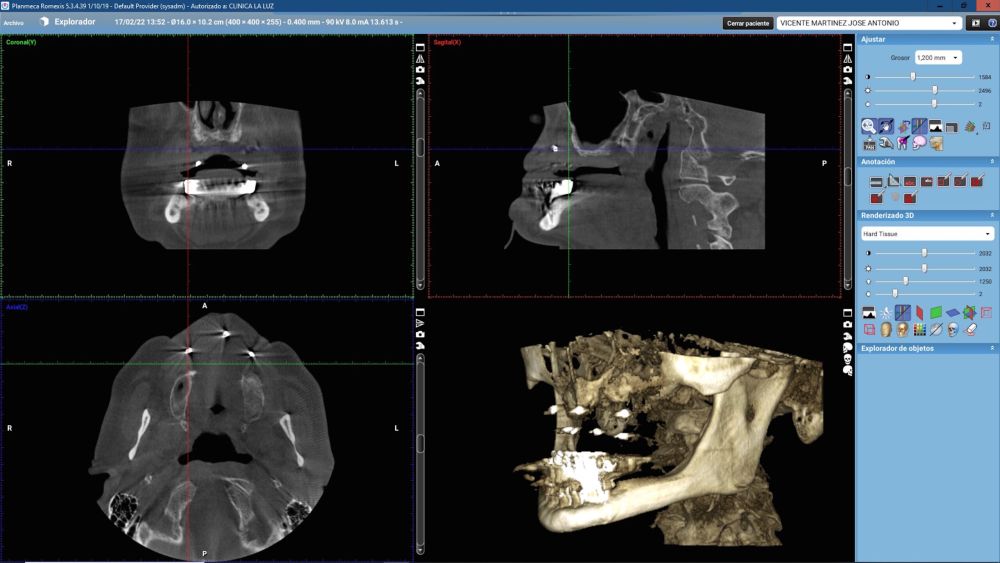

Introduction: Customized subperiosteal titanium implants, designed from planning and fabrication software, constitute an alternative in the rehabilitation of severe maxillary atrophy, avoiding more complex bone and soft reconstruction surgeries and reducing healing times. The aim of this article is to present the rehabilitation in a clinical case with severe atrophy in the upper jaw, using a structure with subperiosteal implants, by means of a digital protocol.

Clinical Case: A subperiosteal sintered titanium structure was fabricated with six transepithelial connections that were rehabilitated with an immediate implant supported fixed prosthesis made of PMMA. Two months later, a sintered chromium-cobalt framework with machined bases covered with acrylic resin teeth was fabricated as the final restoration. At one year follow-up, the case remains stable.

Subperiosteal implants (SI) were developed in Sweden in the early 1940´s. The SI consisted of a custom-made implant, inserted under the periosteum and fixed with screws and the mucous tissue that covered it3,4. They were manufactured in chromium-cobalt or titanium alloys and were rehabilitated by transmucous pillars that emerged in the oral cavity5. Although they were used for years in cases of maxilla atrophies, they were replaced by endoosseous implants designed by Branemark6. This was due to its complex manufacturing. It was necessary to take an impression of the residual bone ridge, which was sent to the laboratory for the structure design, with the consequent imbalances since they were not very stable models. In this way, its placement in the patient was very difficult, and several complications could appear7,8. However, advances in the planning and manufacturing field with various materials have allowed these structures to be made digitally with an excellent predictability and fit, thus avoiding more complex surgeries9.